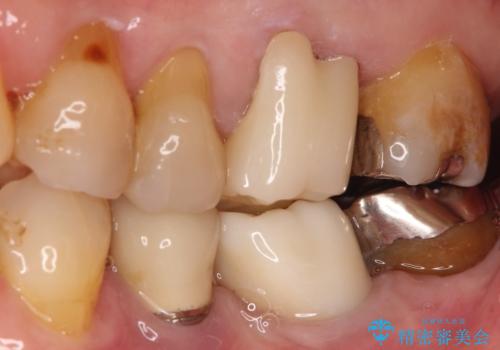

発見の難しい虫歯。根管治療から被せもの治療

- 定期検診にて被せものと歯との隙間に虫歯を発見した患者様です。

根管治療から被せもの治療(ベレッツァ)まで行いました。(根管治療は林院長に依頼)

妥協せずにすべての治療を行うことで最終的な被せものの適合を高める事ができます。